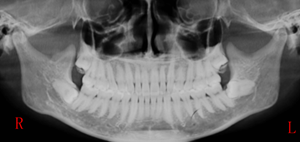

平時拔下頜智齒時看到患者的X片,你知道怎么分析阻生牙的阻力嗎?你知道用什么樣的流程能在最短的時間內(nèi)拔出阻生牙嗎?

答:本x線片示48近中低位埋伏阻生,且牙根緊鄰下牙槽神經(jīng)管,拔除時需注意充分去除近中方向的牙體冠方阻力及遠(yuǎn)中的牙槽骨阻力,挺出牙根時盡量做到一次完成,減少牙根與神經(jīng)管的摩擦,降低神經(jīng)受損風(fēng)險。